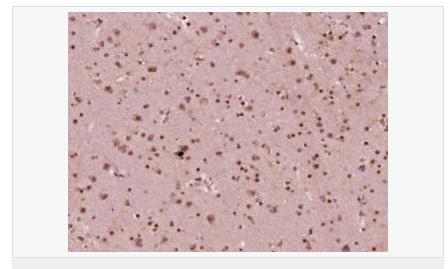

image.png